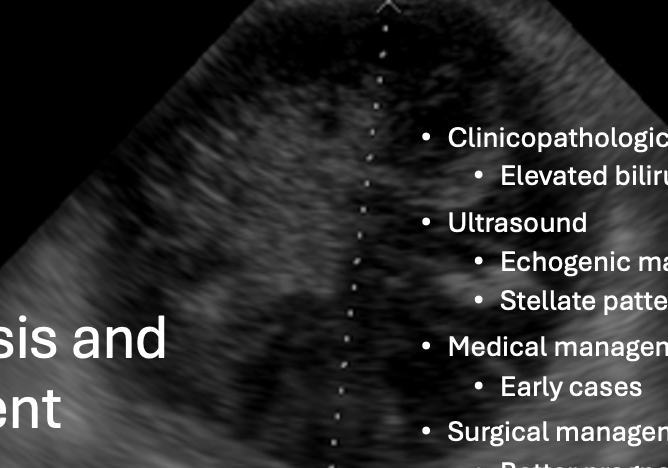

How are gall bladder mucoceles diagnosed?

- Clinicopathologic abnormalities: Elevated bili, ALP, ALT, and AST

- US: Non-dependent echogenic material in a stellate pattern (looks like a kiwi)

How are gall bladder mucoceles managed?

- Medical management for early cases

- Surgical management with cholecystectomy (ensure CBD patency)

What is the prognosis for gall bladder mucoceles managed surgically?

- Better prognosis if not obstructed or showing clinical signs (i.e. "elective" type cases which involve normal bilirubin, have no obstruction or ductal distention, but have a mucocele -> mortality <5%)